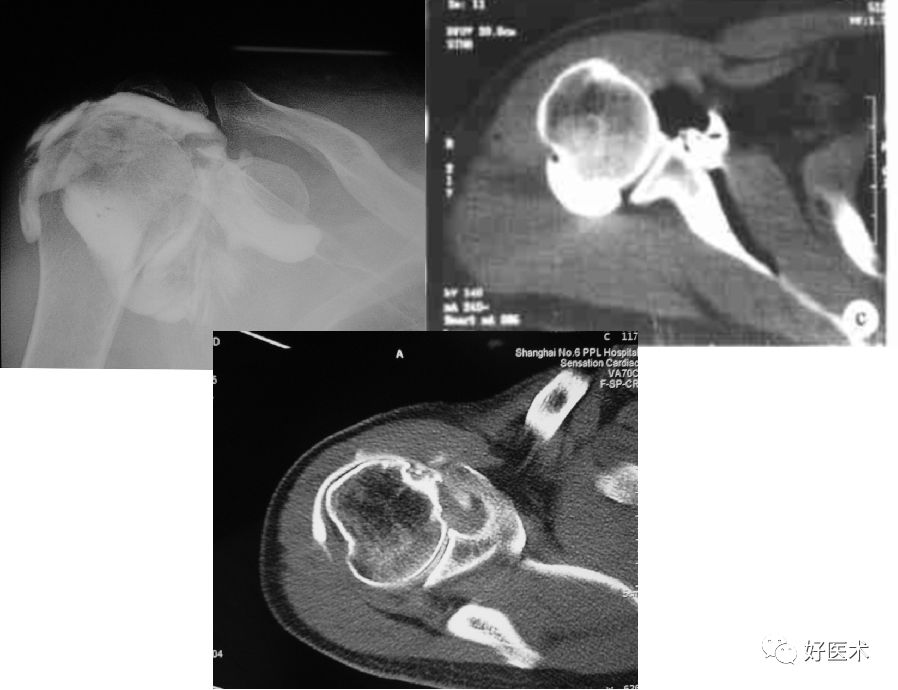

五、CT检查

-

能很好地观察关节的稳定性、骨皮质连续性,可以观察不易发现的关节内骨片

准确评估骨性Bankart病变、Hill-sachs病变

显示软组织结构分辨率较差

CT显示肩关节不稳

后脱位:反Hill-Sachs损伤

后关节盂撕脱小骨折

CT关节造影

显示盂唇损伤及关节囊韧带复合体损伤阳性率很高

为侵入性检查方式,有并发症

对软组织分辨率较低,需要加压注入空气使造影剂均匀弥散到组织表面

CT肩关节造影